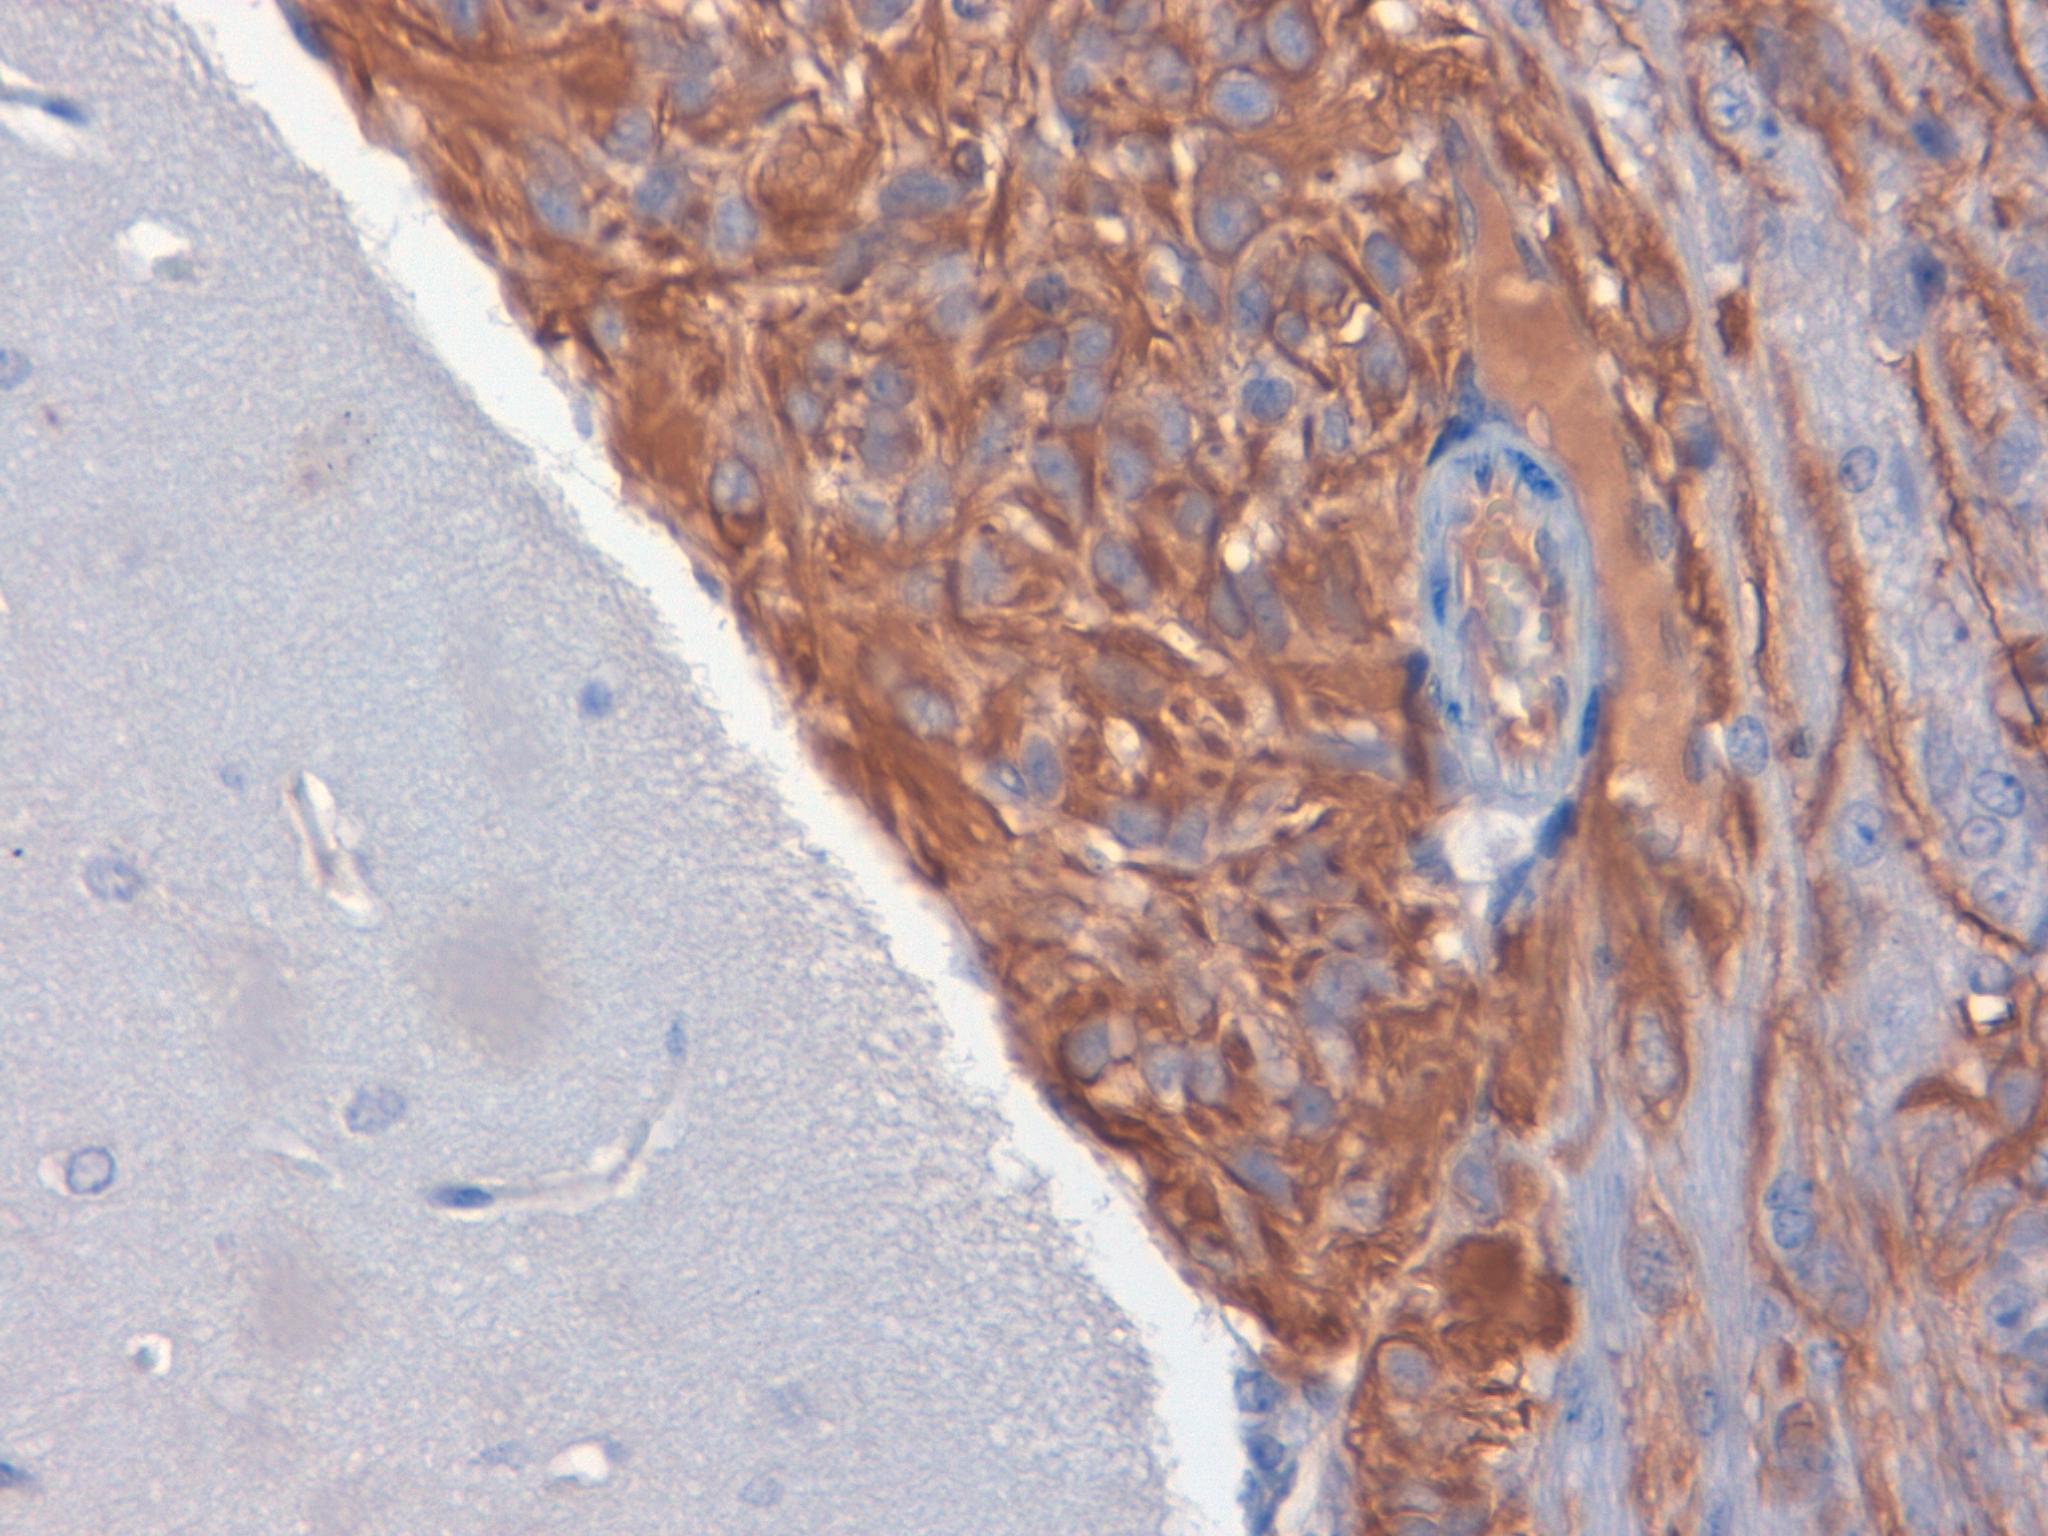

Nestin Nervous Xenograft 40X